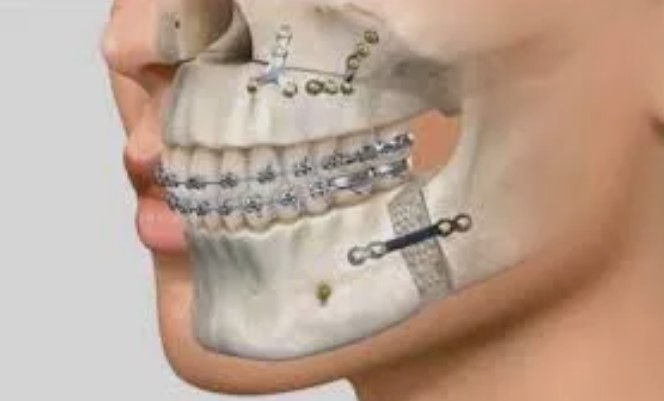

Используемые материалы также влияют на формирование прайса. В современной стоматологии применяются высокотехнологичные сплавы, мини-пластины и винты для фиксации челюстей, которые варьируются по стоимости в зависимости от производителя и класса. Клиники, сотрудничающие с ведущими поставщиками медицинских материалов, формируют прайс с учётом качества и надёжности компонентов.

Главной тенденцией становится широкое внедрение цифровых технологий. Компьютерная томография высокого разрешения, 3D-моделирование, виртуальное планирование операции – всё это позволяет точно прогнозировать результат и сократить время самой операции. Использование CAD/CAM-технологий обеспечивает высочайшую точность изготовления хирургических шаблонов и фиксаторов, что заметно сказывается на безопасности и эстетике итогового результата.

Современные протоколы ортогнатической хирургии предусматривают минимально инвазивные техники, сокращающие сроки госпитализации и реабилитации. Операции всё чаще выполняются под контролем мультидисциплинарной команды, что исключает технические и функциональные ошибки. Фокус смещается на функциональное восстановление: важно не только исправить прикус, но и добиться гармонии лица, свободного дыхания, правильной работы мышц и суставов.